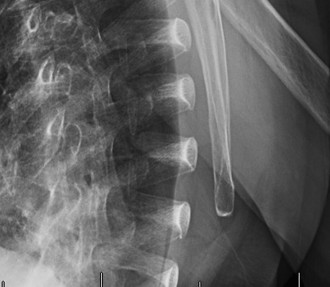

CT arthrograms of the patient’s left shoulder are shown in Figure 2–56. CRP is <3, ESR 45. The patient continues to have pain, so you decide to perform arthroscopic biopsy to obtain tissue cultures. Frozen sections show <5 PMNs per hpf, and Gram stains are all negative.

Figure 2–56

The correct answer is (B). Figure shows contrast under the glenoid component. Given the patient’s normal inflammatory markers and frozen sections combined with continued pain and loosening on CT, infection with P. acnes(an organism that is very difficult to isolate) should be investigated by holding any cultures for at least 2 weeks to see if it will eventually grow. Chocolate agar (Choice C) is mainly used for growing species such as H. influenzae and Neisseria meningitidis not P. acnes. A is incorrect since the patient’s cell count and frozen sections are clearly abnormal, therefore referral to pain clinic would not be appropriate. However, Choice D would be too aggressive an approach given that no organisms have been isolated, frozen sections show <5 PMNs per hpf, and the patient has relatively normal inflammatory markers.